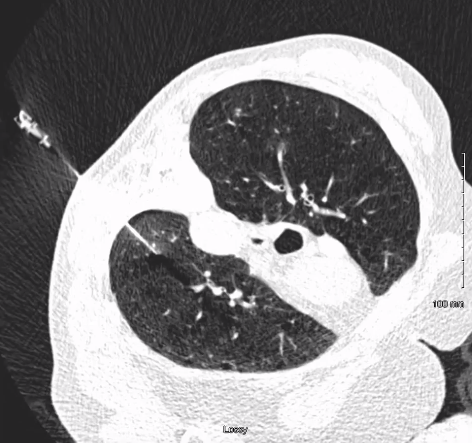

在手术过程中,CT成像显示,一旦穿刺针穿过胸膜,几乎立即发生气胸。然而,由于有经皮胸腔引流患者无气胸症状,并能忍受手术。手术成功,获得了高质量的病灶核,为病理诊断提供了依据。患者对手术耐受良好,并于摘除引流管后第二天出院。 |